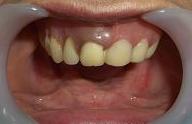

治療前

A 70代女性     患者さんの、「下あごの土手がなくなり、入れ歯がすぐに動いてしまうので、とっても使い勝手が悪いのですが、動かないようにできないでしょうか?」という訴えのもと、CT撮影により、下顎骨の状態を確認の後、ミニインプラントを4本植立しました。

下の総入れ歯をしっかり固定することができたので、入れ歯安定剤の使用は不要になりました。